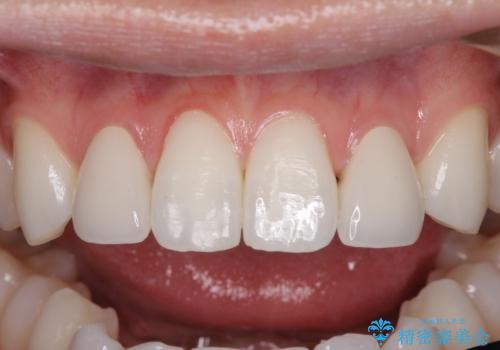

ホワイトニングを併用し、治療前と比べて自然でとても明るい口元となりました。